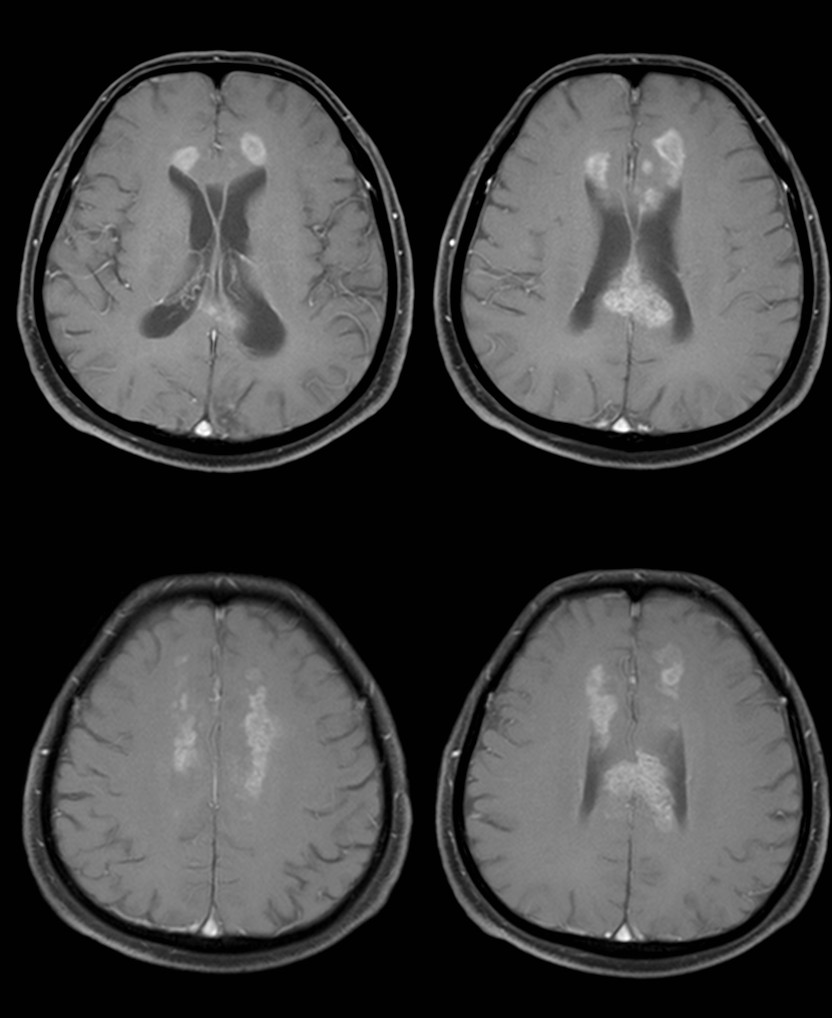

31岁,男性,长期饮酒,出现急性失语、短期注意力和记忆力缺陷,胼胝体及半卵圆中心对称性异常信号,扩散受限,未见强化,经过维生素B1/6/9/12治疗后病灶吸收明显,诊断为原发性胼胝体变性急性期。

48岁,男性,长期饮酒过量20年,出现出现眩晕,胼胝体、侧脑室周围白质、内囊后肢对称性异常信号,扩散受限,诊断为原发性胼胝体变性急性期。

胼胝体压部病变及多发皮层对称性病变,表现为扩散受限